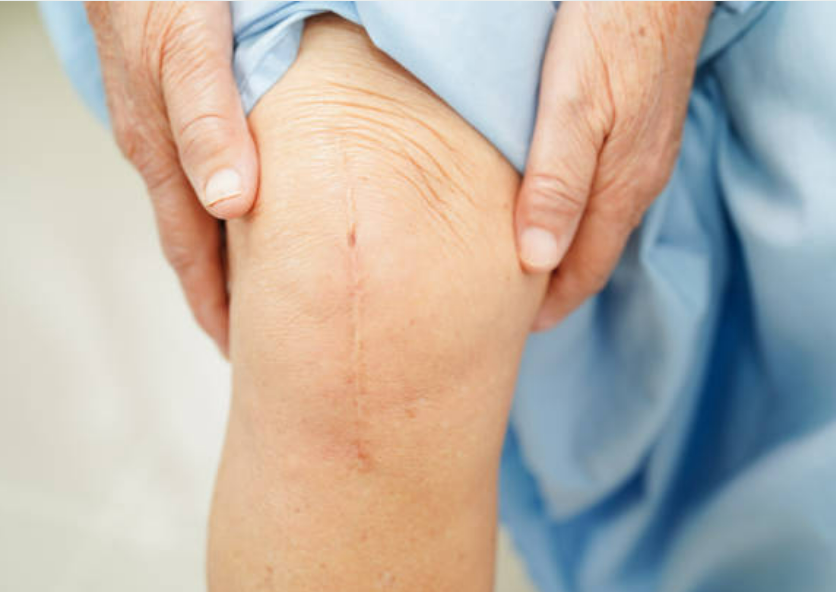

관절의 변형: 마지막으로 조심해야 할 관절염의 징후

진행된 관절염은 관절의 형태와 구조에 변화를 가져올 수 있습니다. 이는 관절의 형태의 변형이나 골절을 초래할 수 있으며, 심각한 경우 관절 운동에 심각한 제한을 초래할 수 있습니다.

관절염을 예방하고 치료하는 방법

관절염을 예방하고 치료하기 위해서는 일상 생활에서 관절에 대한 부담을 줄이는 것이 중요합니다. 체중 관리, 균형 잡힌 식단, 균형 잡힌 운동 및 근력 강화 운동은 관절염 예방에 도움을 줄 수 있습니다. 또한, 약물 치료, 물리 치료 및 수술 등의 치료 옵션도 고려해야 합니다.